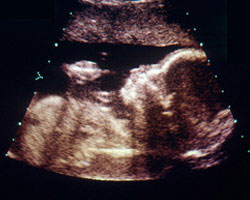

De certeza que tens vontade de ver como é, aproximadamente, o teu bebé durante esta semana. Aqui tens uma ecografia e um vídeo correspondentes à 23ª semana, para que o possas ver em movimento. Maravilhoso!

Ecografia de 23 semanas